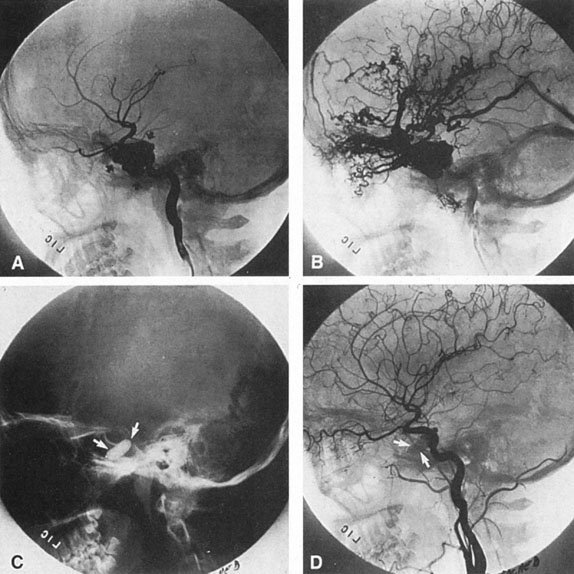

The detection of intracranial AVMs is facilitated by CT scanning and MRI (Fig. 10),88 but optimal management requires selective angiography89 that assesses the size and configuration of the mass, the number and location of feeding arteries, the flow characteristics and degree of steal from brain parenchyma, and the pattern of venous drainage.

Fig. 10. Neuroimaging of arteriovenous malformation. A: Coronal magnetic resonance imaging (MRI) (TR, 600 ms; TE, 20 ms) shows wedge-shaped vascular mass extending from the surface of the parietal cortex (white arrows) to the lateral ventricle (black arrows; asterisk, arterial feeder). B: Posteroanterior left arteriogram of the same lesion. C: Axial computed tomography scan with contrast enhancement. D: Axial MRI of a large arteriovenous malformation, first echo (TR, 2000 ms; TE, 20 ms). E: Second echo (TR, 2000 ms; TE, 90 ms). (From Smith HJ, Strother CM, Kikuchi Y, et al: MR imaging in the management of supratentorial intracranial AVMS. AJNR Am J Neuroradiol 9:225, 1988.)

The natural history of unruptured intracranial AVMs is somewhat controversial,65,67 the issue being conservative management of interventional therapy using refined microsurgical or embolization techniques. Brown and associates90 reviewed the experience of the Mayo Clinic, Rochester, Minnesota, from 1974 through 1985, with a minimal follow-up of at least 4 years after diagnosis (mean follow-up time, 8.2 years). Of 168 patients, 18.5% had an intracranial hemorrhage, with an overall risk of hemorrhage of 2.25% per year (vs. 4%, as reported by Ondra et al65), and observed annual rates of hemorrhage increased over time. The mortality rate from hemorrhage was 29%. Of 22 patients with nonfatal intracranial hemorrhages, 14 did not undergo treatment and none of these had recurrent hemorrhage during the mean follow-up of 58 months. No radiologic or clinical features seem consistently helpful in predicting rupture. According to Pollock et al,61 analysis of clinical and radiologic features revealed 6 signficant risk factors for hemorrhage: (i) history of prior bleeding; (ii) deep location; (iii) deep venous drainage; (iv) increasing patient age; (v) diffuse morphology (versus compact nidus); and (vi) single draining vein. Based on these findings, these authors concluded that annual bleeding for the low-risk group was 1.0%, and it was 9.0% for the highest risk group.

The therapy for AVMs has been reviewed elsewhere.91–93 The preferred treatment remains complete surgical excision of the malformation. However, significant advances in endovascular and radiosurgical techniques have resulted in a marked increase in the use of multimodal, staged approaches to AVM treatment. A variety of intravascular techniques use embolization91 with materials such as particles of polyvinyl alcohol (PVA), platinum coils, and injection of liquid N-butyl-cyanoacrylate (NBCA) adhesive (Fig. 11). Complications of intravascular embolotherapy include vessel perforation by the catheter, migration of embolic materials, and infarction and hemorrhage of normal brain.

Fig. 11. Embolization of middle cerebral vessels that supply occipital lobe arteriovenous malformation (AVM). The patient had a subarachnoid and intraparenchymal hemorrhage that produced a left homonymous field defect. A: Right carotid arteriogram demonstrates contribution via posterior communicating artery to a right occipital lobe AVM. B: Vertebral injection. The arrow points to the enlarged right posterior cerebral artery that is a major feeder of the AVM. C: Right carotid arteriogram during glue embolization procedure. The arrow points to a catheter as it traverses the segment seen in (B). The catheter was advanced via the internal carotid artery but is positioned far posteriorly. D: Upper branches to the AVM now are occluded, with residual low-flow vascularization via the middle cerebral artery. E: Skull film showing radiopaque glue within the AVM and blood vessels previously supplying it. The patient had a persistent visual field defect but greatly reduced headache and no persistence of subjective bruit. (Courtesy of Dr. Joseph Horton.)